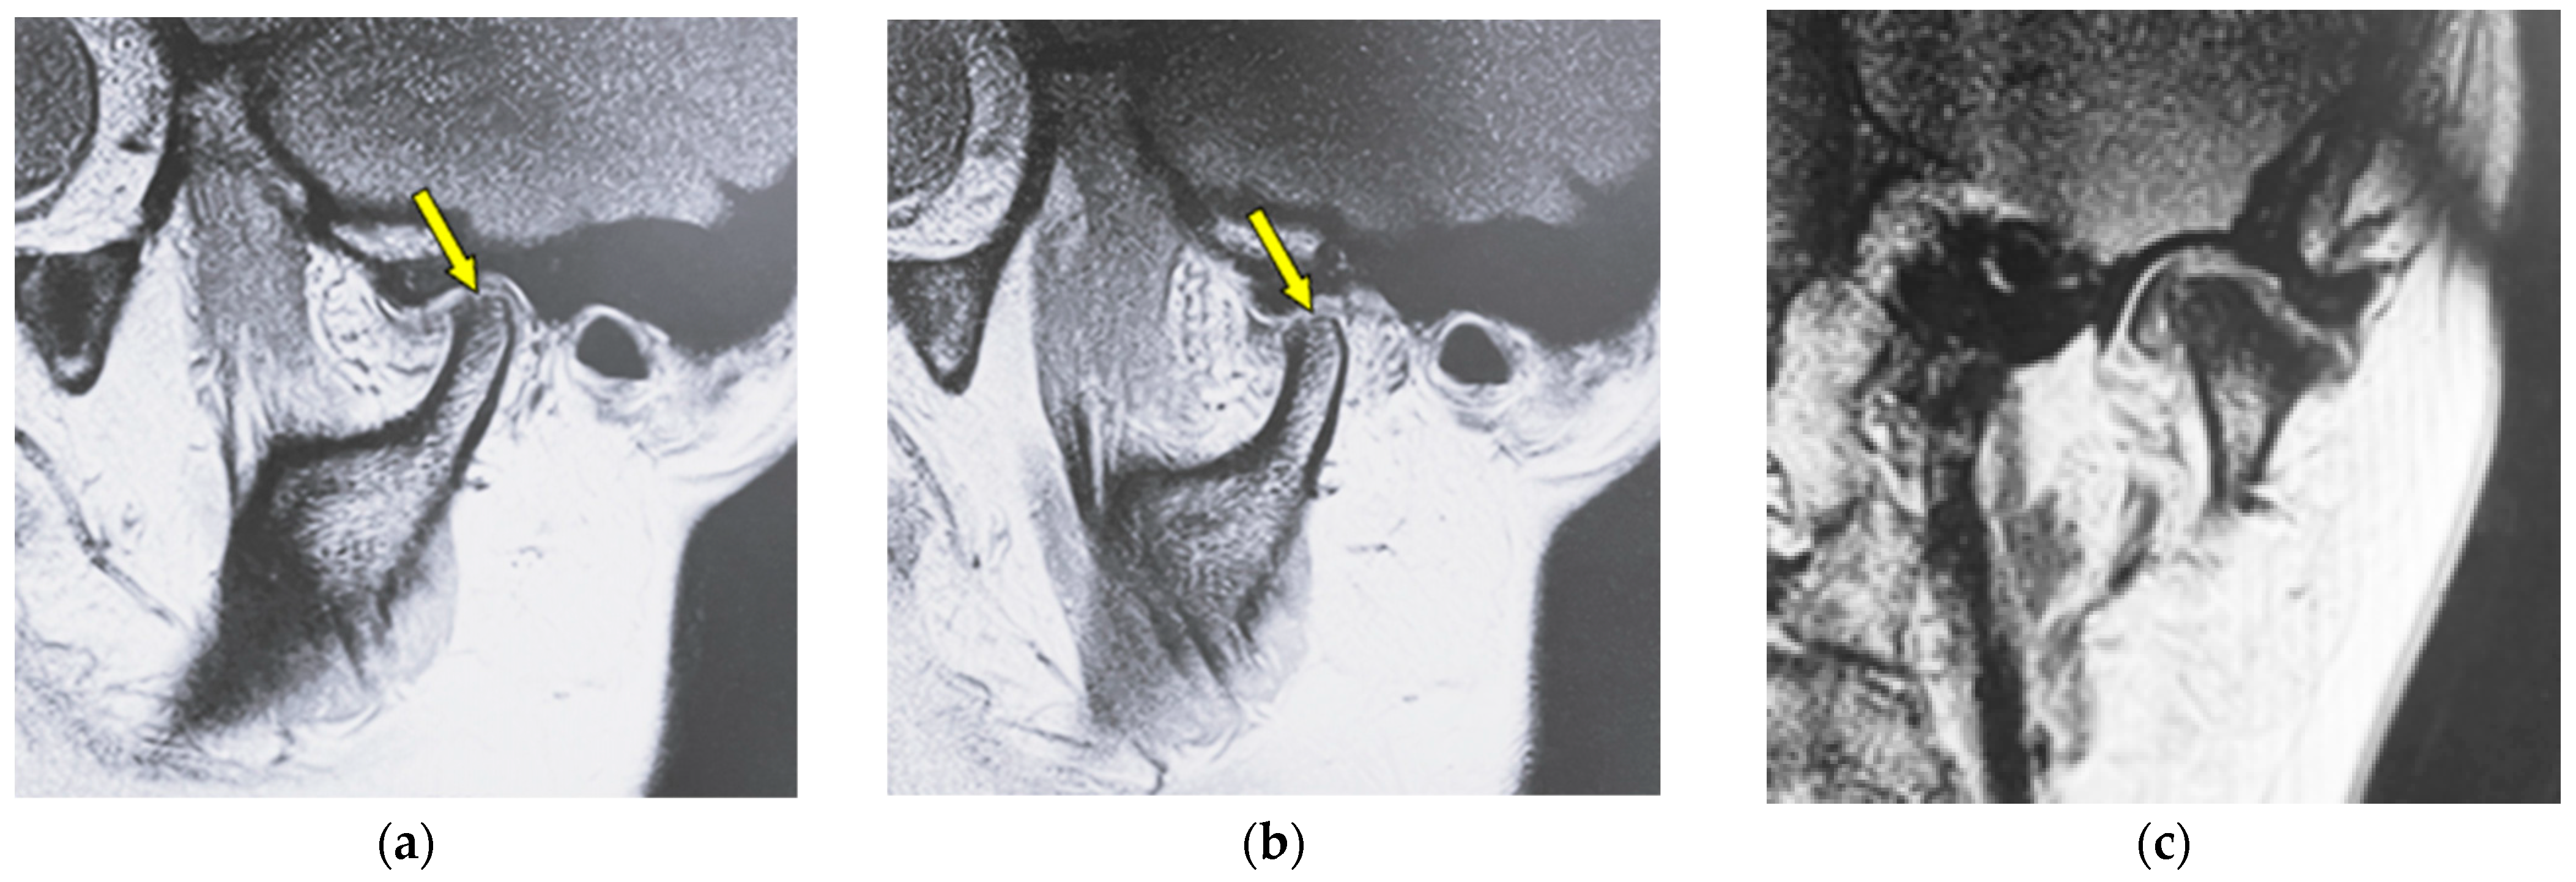

| Erosion | Local area of rarefaction in compact bone with a lack of cortical bone continuously |